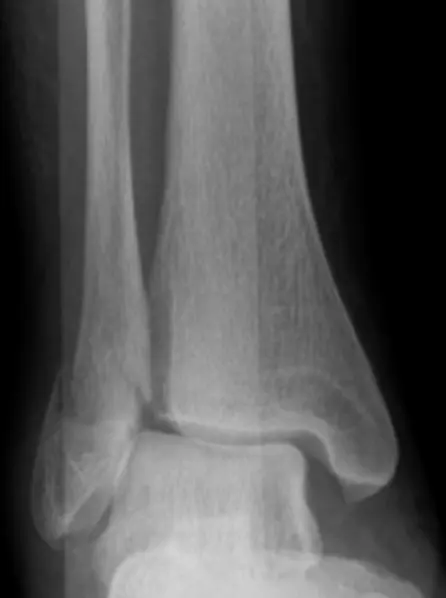

Patient: 32âyearâold male with a severe twisting ankle injury â painful, swollen and unable to stand.

Findings

- Site: lateral malleolus

- Fracture type: simple

- Fracture line: spiral

- Displacement: gap medially

- Special issue: possible ruptured deltoid ligament